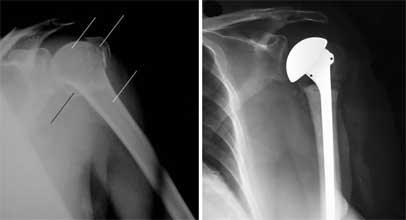

درمان جراحی شکستگی مفصل آرنج در ناحیه سوپراکندیلر

در صورتیکه قطعات شکسته شده جابجا شده باشند درمان جراحی است. در اطاق

عمل بیمار تحت بیهوشی عمومی قرار گرفته و یا کل اندام فوقانی وی بیحس میشود.

پزشک جراح ارتوپد با شکافتن پوست و کنار زدن عضلات، محل شکستگی را در

دید مستقیم خود قرار داده و پس از کنار هم قرار دادن قطعات شکستگی، آنها را به یکدیگر

به توسط وایر یا پیچ و پلاک متصل میکند. زخم بسته میشود و تا مدتی کل اندام فوقانی

بیمار توسط یک اتل محافظت میشود.

گاهی اوقات اگر شکستگی خیلی خرد باشد و سن بیمار زیاد باشد پزشک معالج

تصمیم میگیرد تمام قطعات شکسته شده را خارج کرده و مفصل آرنج را با یک مفصل مصنوعی

جایگزین کند.